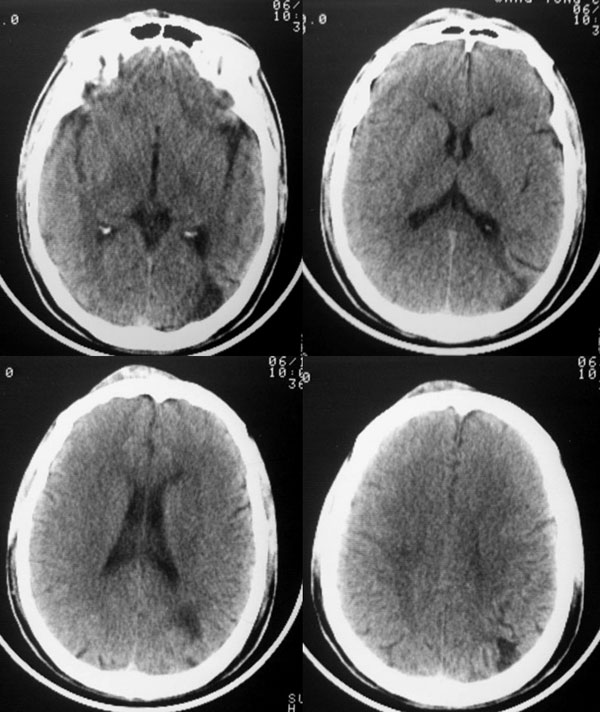

以下是引用dyqct在2006-11-9 15:04:00的发言:[br]左枕叶、双顶叶各见一处似三角形低密度区,边界尚清楚,无占位效应,累及皮质,白质侧未见灰质影。余所见未见异常。[br]考虑:1、脑软化灶;[br] 2、不支持脑裂畸形,该病病变区两侧应有灰质带——即灰质异位,临床上常有顽固性颠痫。当然了脑软化灶也偶会出现颠痫。

以下是引用守望可可西里在2006-11-9 15:06:00的发言:[br][br] 1.左侧枕叶低密度与侧脑室相通,考虑开唇型脑裂畸形。[br] 2.双侧顶叶低密度考虑局部脑沟异常扩大,发育问题。